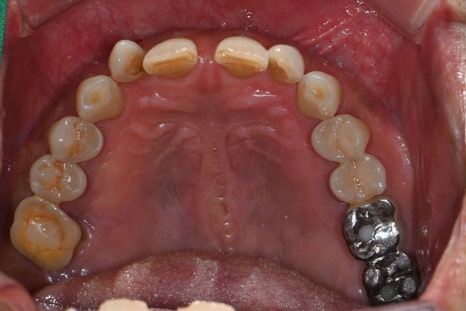

Left photo: panoramic X-ray taken at the patient’s first visit.

Right photo: initial intraoral photo showing the condition of the gums and teeth in the molar area.

The large molar at the very back had already been missing at the first visit, and the molar in front of it had severe periapical inflammation.

In addition, the small molar was severely mobile, so both teeth were extracted and replaced with implants, while overall gum treatment was also performed to establish the treatment plan.